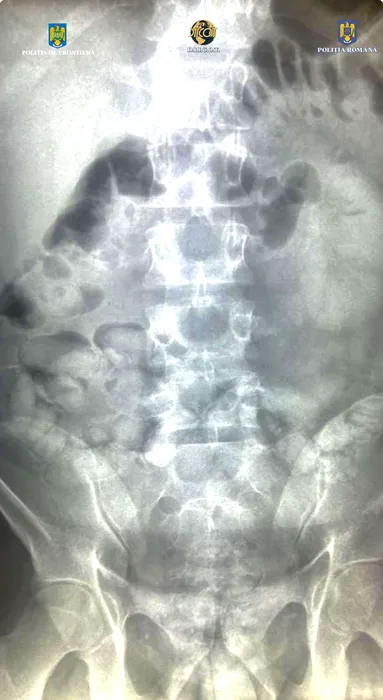

Un tânăr brazilian a fost prins cu COCAINĂ pe Aeroportul Otopeni. Unde ascundea drogurile și ce cantitate avea asupra sa